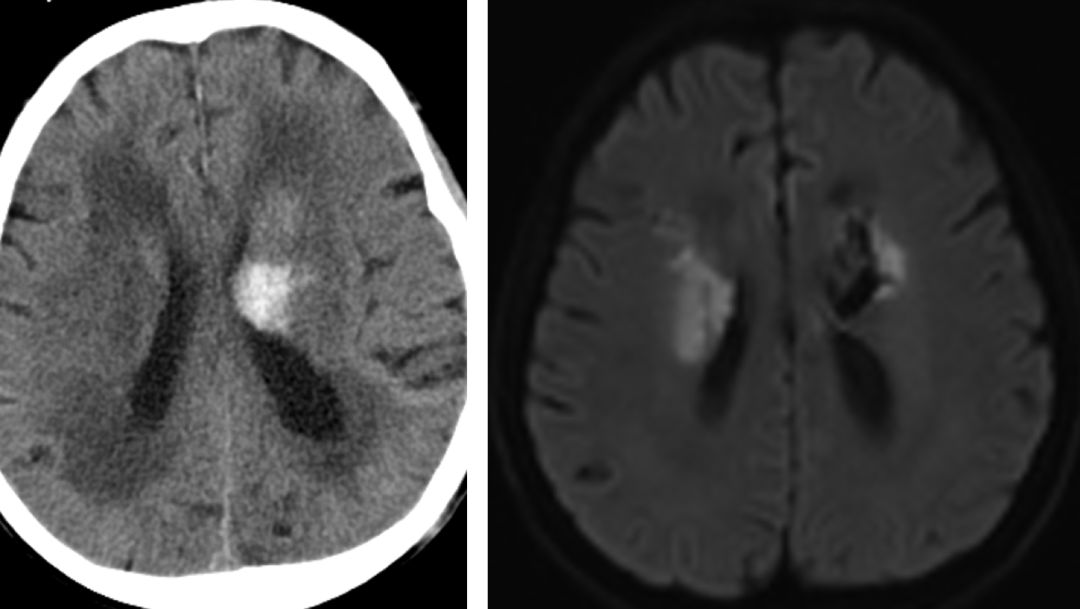

次日复查头颅 CT 提示左侧基底节区出血!

进一步完善头颅 MRI + MRA:左侧脑室旁脑出血伴双侧脑室后角积血;双侧脑室旁及半卵圆中心急性梗死;右侧半卵圆中心及右侧基底节区软化灶,脑白质脱髓鞘改变;头颅 MRA 示颅内动脉硬化改变,未见明显狭窄闭塞。